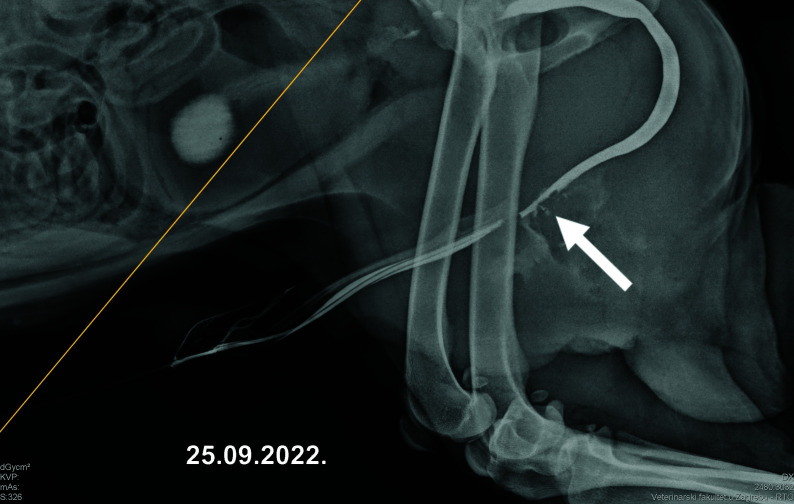

我们报告了一例因输尿管结石而导致尿道瘘的两岁雄性狗,品种为秋刀鱼。术中用亚甲蓝确定了尿道缺损。由于众所周知尿道壁在这种情况下会出现愈合问题,因此采用了自体再生法与手术闭合缺损相结合的方法。对部分腹部脂肪组织进行了解剖,以产生含有间充质干细胞的微碎脂肪组织,并将其与富血小板血浆相结合。最终产品被应用于尿道缺损闭合区周围。术后一个月,膀胱造影阳性对比证实了伤口愈合。这种治疗方法取得了成功,一年的随访期间一切顺利。在犬类模型中观察到的这种方法的积极成果可被视为研究该疗法在人类医学中转化潜力的起点。

We report on a case of a two-year-old male dog, breed chow-chow, who suffered from urethral fistula as a result of ureterolithiasis. The urethral defect was identified intraoperatively with methylene blue. An autologous regenerative approach was combined with surgical closure of the defect, due to the well-known healing issues of the urethral wall in such conditions. A part of abdominal fat tissue was dissected to produce microfragmented adipose tissue containing mesenchymal stem cells, which was combined with platelet-rich plasma. The final product was applied in the area around the urethral defect closure. One month after the procedure, healing was confirmed with positive-contrast cystography. This therapeutic approach yielded success, and the follow-up period of one year was uneventful. The observed positive outcome of this approach in the canine model may be considered as a starting point for investigating the translational potential of the treatment in human medicine.